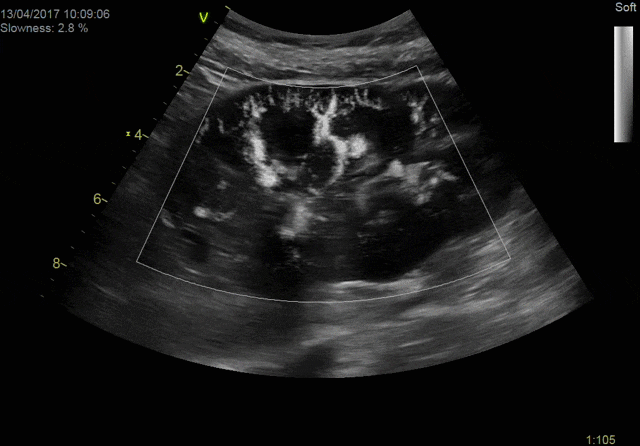

Экспертное качество изображений при проведении 2D TTE исследований и при обычной трансторакальной эхокардиографии дает возможность проводить сложные кардиологические исследования и получать достоверные результаты для назначения эффективного лечения.

Благодаря своим техническим возможностям система Vivid S70 позволяет получать достоверные данные для количественной оценки даже при проведении исследований пациентам с избыточным весом или пациентам состояние которых затрудняет проведение диагностики, а технология датчиков XDclear работающая в паре с платформой cSound гарантирует беспрецедентный уровень качества изображений.